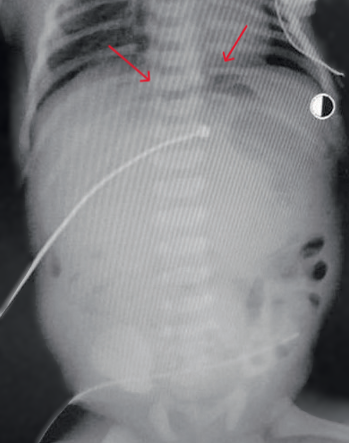

В возрасте 37 часов жизни с диагнозом кишечная непроходимость, перфорация полого органа для хирургической помощи перегоспитализирован в реанимационное отделение новорождённых ОДКБ в тяжёлом состоянии на ИВЛ. На рентгенограммах органов брюшной полости выявлен симптом «серпа», характерный для пневмоперитонеума (рис. 4).

|

Рис. 4. На рентгенограммах органов брюшной полости характерный признак пневмоперитонеума – симптом «серпа»